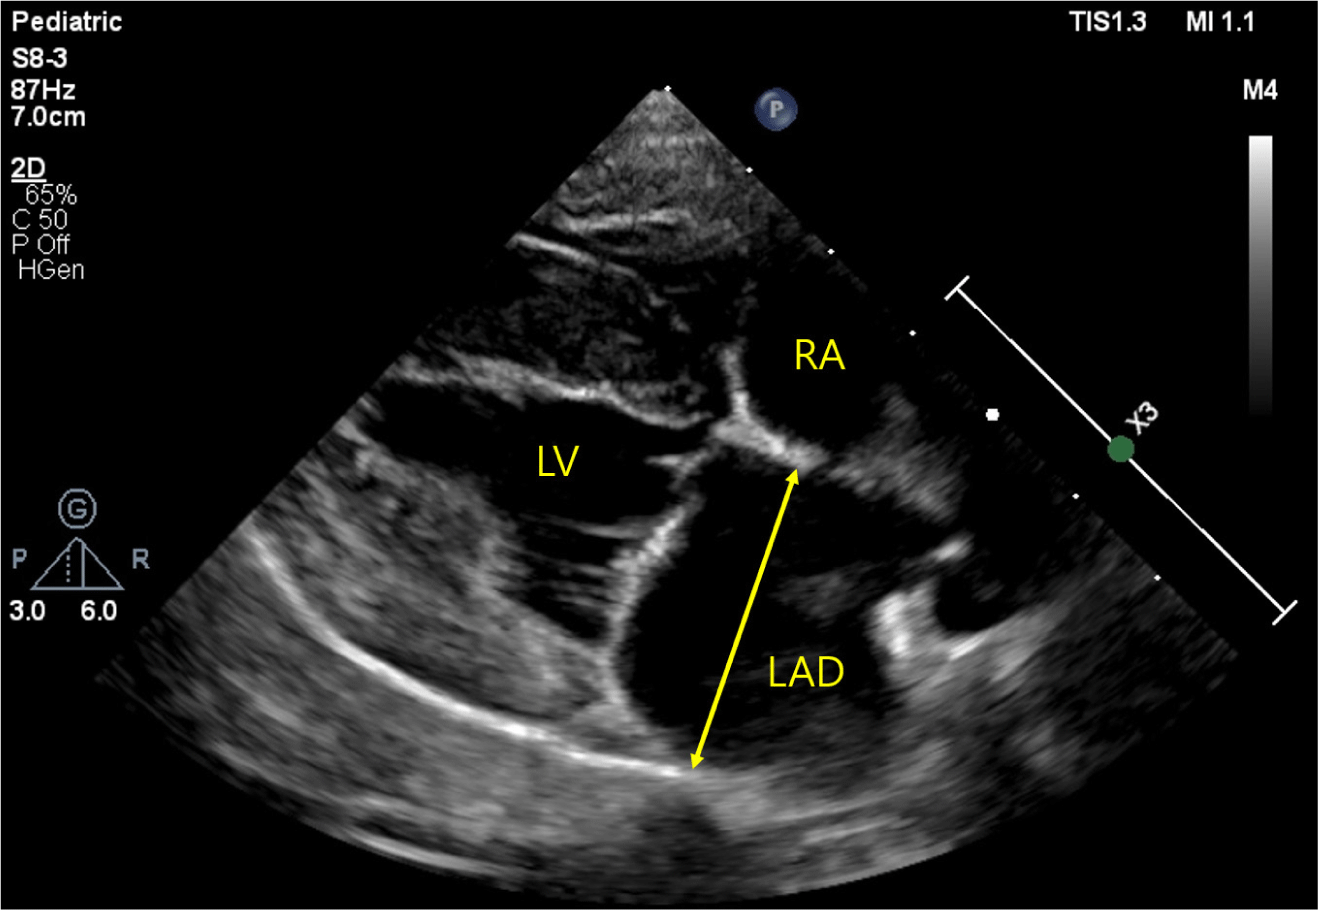

Correlation between left atrial anteroposterior diameter and N-Terminal pro-brain natriuretic peptide (NT-proBNP) in dogs with myxomatous mitral valve disease

J Biomed Transl Res 2025;26(3):69-77.

https://doi.org/10.12729/jbtr.2025.26.3.69